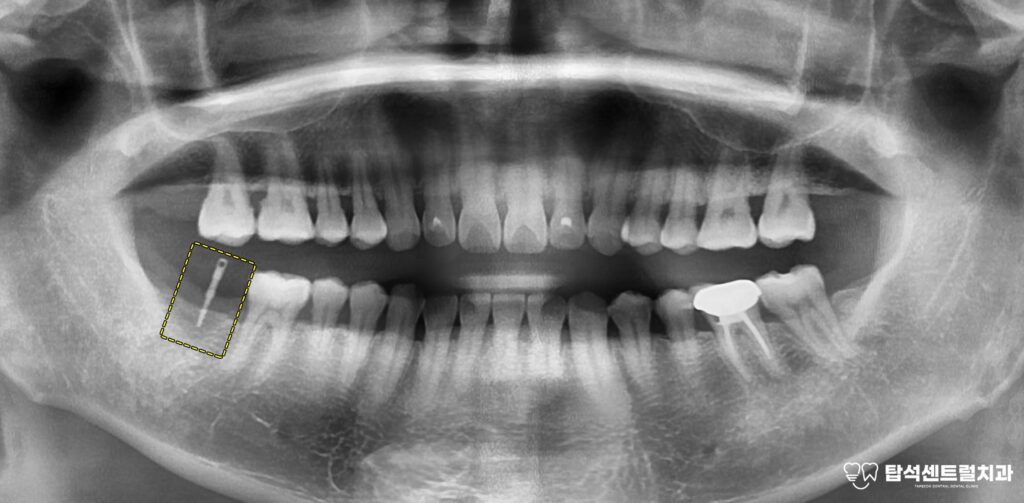

구강 검진과 문진만으로는

치아 자체의 이상이 발견되지 않을 때

엑스레이 촬영을 통해 주변 구조물을

함께 확인하게 됩니다.

엑스레이에서 의심 소견이 보이면

CT 촬영을 추가로 진행하여

상악동 내부 상태를 정밀하게 살펴봅니다.